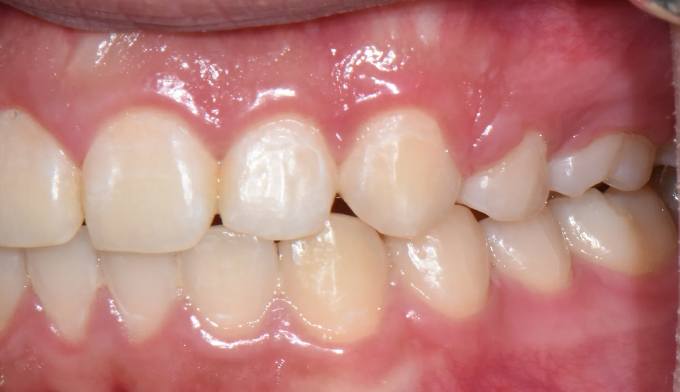

앞니가 돌출되어 있으면서 동시에 위 맨끝 어금니가 아래 어금니와 사선으로 물려있는 가위교합이 관찰됩니다.

가위교합은 음식물 섭취에 있어서도 비효율적이지만, 올바른 잇솔질을 하기가 어려워 구강위생에도 좋지 않아 교정이 필요합니다.

돌출입을 해소하고 동시에 가지런하지 못한 치열을 바르게 펴서 양치하기 좋은 상태로 만들어줍니다.

총 교정기간은 23개월입니다.